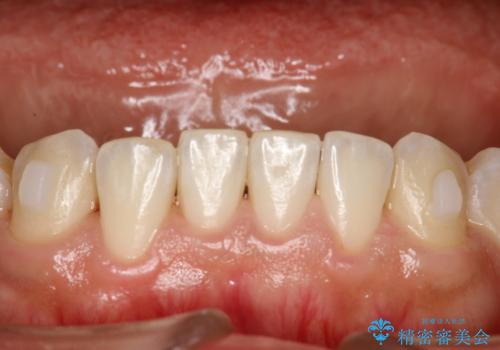

インビザライン中に歯の着色落としクリーニング PMTC

- インビザライン治療中に着色が気になるとのことでクリーニングを希望されました。PMTC30分コースを行いました。

インビザライン治療中には、歯の表面にアタッチメント(効率的に歯の移動をするもの)を設定します。そのため歯ブラシでは届きにくい細かい部分などに、歯石や着色がついてしまうことがあります。着色などを放置していると、着色なのか、虫歯なのかの判別もしずらく正確にお口の中の状態を診断できません。

矯正治療中も定期的に歯科医院にてPMTCを受けて、お口のケアを行うことをおすすめします。